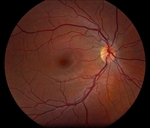

The patient presented with new worsening vision in both eyes. Around one month prior to presentation, he was switched to immunotherapy with ipilimumab, nivolumab, and cabozantinib. Visual acuity measured count fingers in both eyes from a previous 20/80 in the right eye (OD) and 20/200 in the left eye (OS). Intraocular pressure, pupillary exam, and confrontational visual fields were normal. Anterior segment examination was overall unremarkable with clear corneas and trace nuclear sclerotic cataracts bilaterally. Dilated fundoscopic exam showed new mild bilateral vitritis and stable bilateral choroidal lesions with overlying pigmentary changes (Figure 1). Greater subretinal fluid was present in the macula than previously observed. Optical coherence tomography confirmed increased subretinal fluid and revealed a subretinal fibrinoid response (Figure 2).

Figure 1. Color fundus photos showing bilateral choroidal lesions with overlying pigment changes. |

Figure 2. Spectral-domain optical coherence tomography (SD-OCT) demonstrating intraretinal fluid, and subretinal fluid with subretinal fibrinoid response bilaterally. |